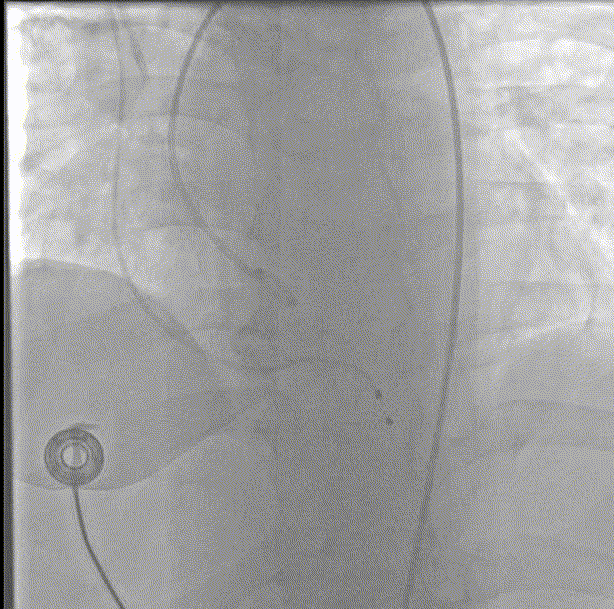

主动脉根部造影

18mm球囊预扩

支架预埋

瓣膜首次定位释放

瓣膜释放至2/3

回收瓣膜再释放

多体位下观察植入深度

释放完成

术后造影

入路造影